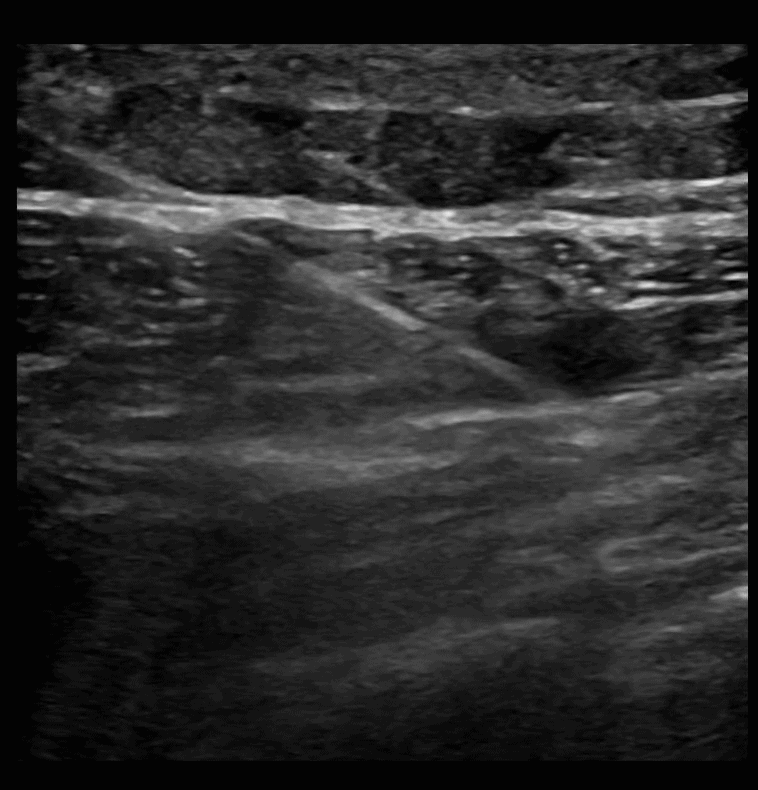

SAPB 3: Needle is guided in long axis from posterior to anterior with the target being the fascial plane that separates the latissimus dorsi muscle from the serratus anterior muscle.